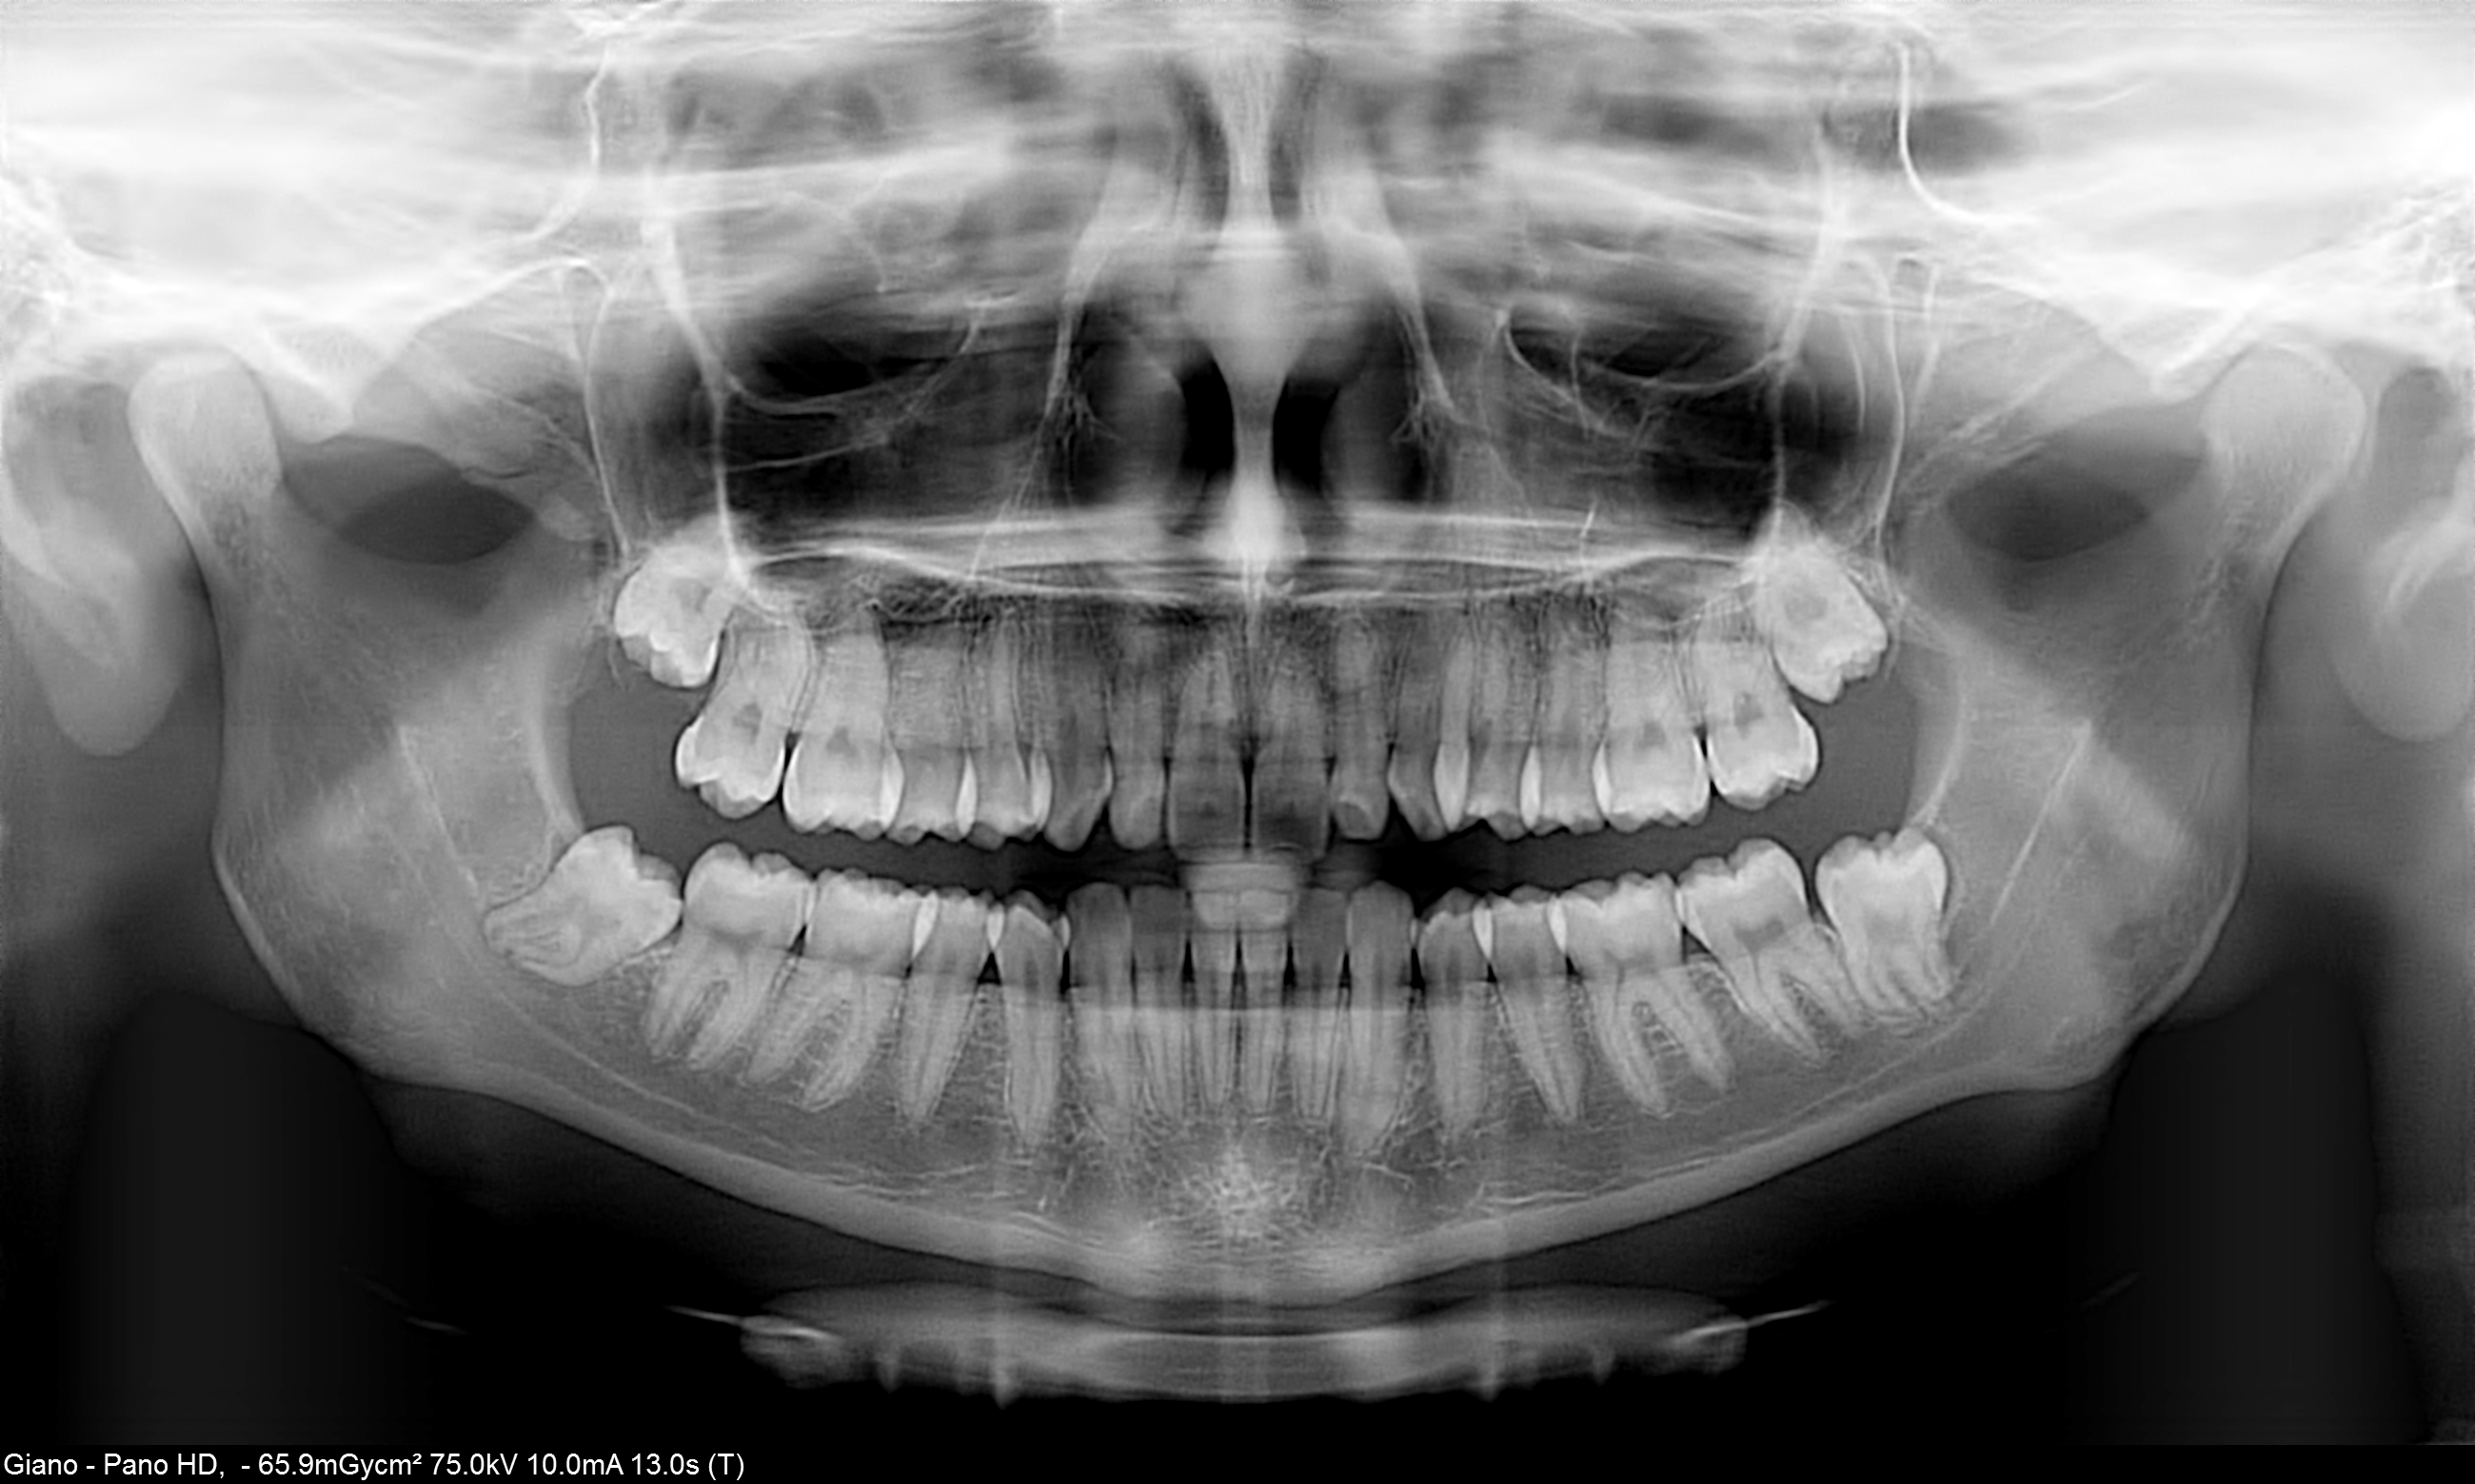

L'esame Ortopanoramico, benché minimalmente invasivo per il suo intrinseco basso dosaggio, a causa della sua natura bidimensionale potrebbe fornire informazioni inaffidabili riguardo la relazione tra il canale alveolare inferiore e le radici dei molari. Infatti in casi molto complessi questa informazione potrebbe essere insufficiente e quindi rendersi necessario un esame più approfondito.

Oggi l'Odontoiatra, grazie alla diffusione delle apparecchiature Cone-Beam 3D, ha la possibilità di effettuare valutazioni accurate, anche in studio, su questo tipo di casi con accuratezza ed affidabilità e con una bassa dose radiogena erogata al paziente.